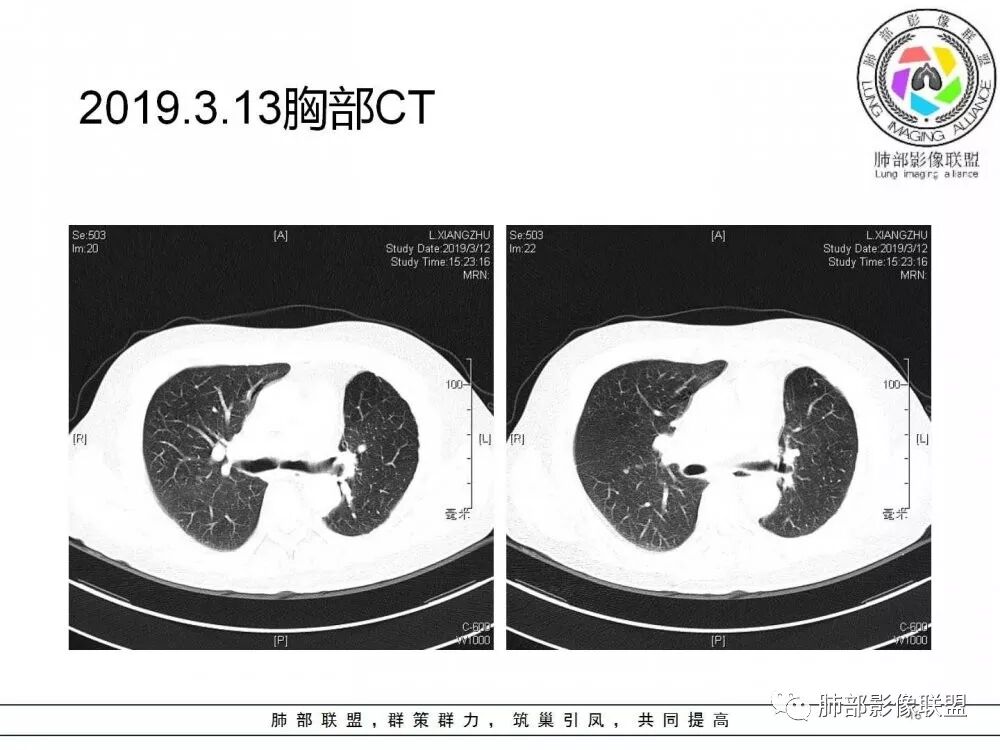

右肺上叶后段实性结节,部分边缘磨玻璃,周围可见多发小结节,病灶逐渐进展,临床有肺癌病史、IgG4相关病变、激素长期使用史,考虑1、隐球菌;2、肺癌复发;3、IgG4相关性肺改变,病变局限,应该不符合。

右肺上叶后段多发实性结节,边缘收缩,葫芦兄弟,临床有激素治疗史,考虑隐球菌。

肺癌病史,长期激素使用史,IgG4相关病史,治疗有抗癌和激素治疗,肺部多发胸膜下小结节,边缘模糊,有些结节有进展,葫芦兄弟,考虑隐球菌。

右肺上叶后段实性结节,周围可见多发小结节,病灶逐渐进展,临床有肺癌病史、IgG4相关病变、激素长期使用史,考虑1、隐球菌;2、肺癌复发;3、IgG4相关性肺改变

肺部病灶从2月份就开始有了,应该最早说是1月7号就有了,到3月13号稍微增大一点,到后面几乎就没变化了,到5月份好像稍微大一些,炎性肯定是炎性,就是这个炎性是到底什么病变呢?其实本没变化,它特点一个是在叶裂上,跟血管关系密切,但是病灶边缘稍收缩,病灶这么没有太大变化,我还是支持炎性病变。